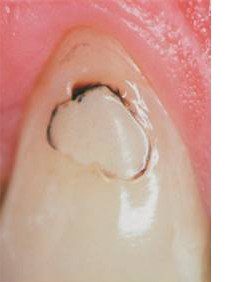

Первый признак, который указывает на появление заболевания – это потемнение эмали в районе пломбы. Затем такое потемнение у себя в полости рта, вам следует немедленно обратиться к специалисту. Пациент может испытывать небольшой дискомфорт или неприятную, ноющую боль. В некоторых случаях разрушение может не проявляться клинически, и его можно обнаружить, только начав лечение.